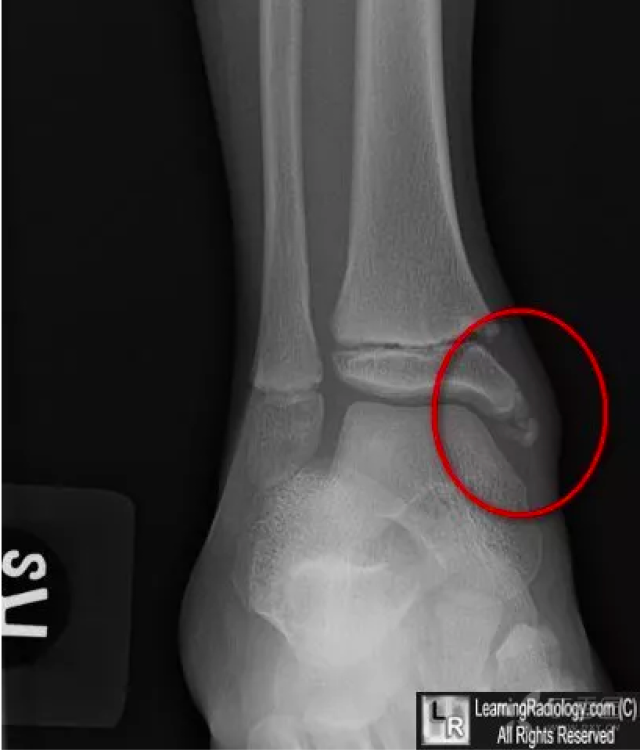

该内踝骨折需要手术吗

a型,内踝尖的撕脱性骨折;b型,骨折线发生在内踝尖和胫骨远端穹隆之间

胫骨内踝的骨骺有多个骨化中心所致,见于儿童,不确定时可做双侧对比